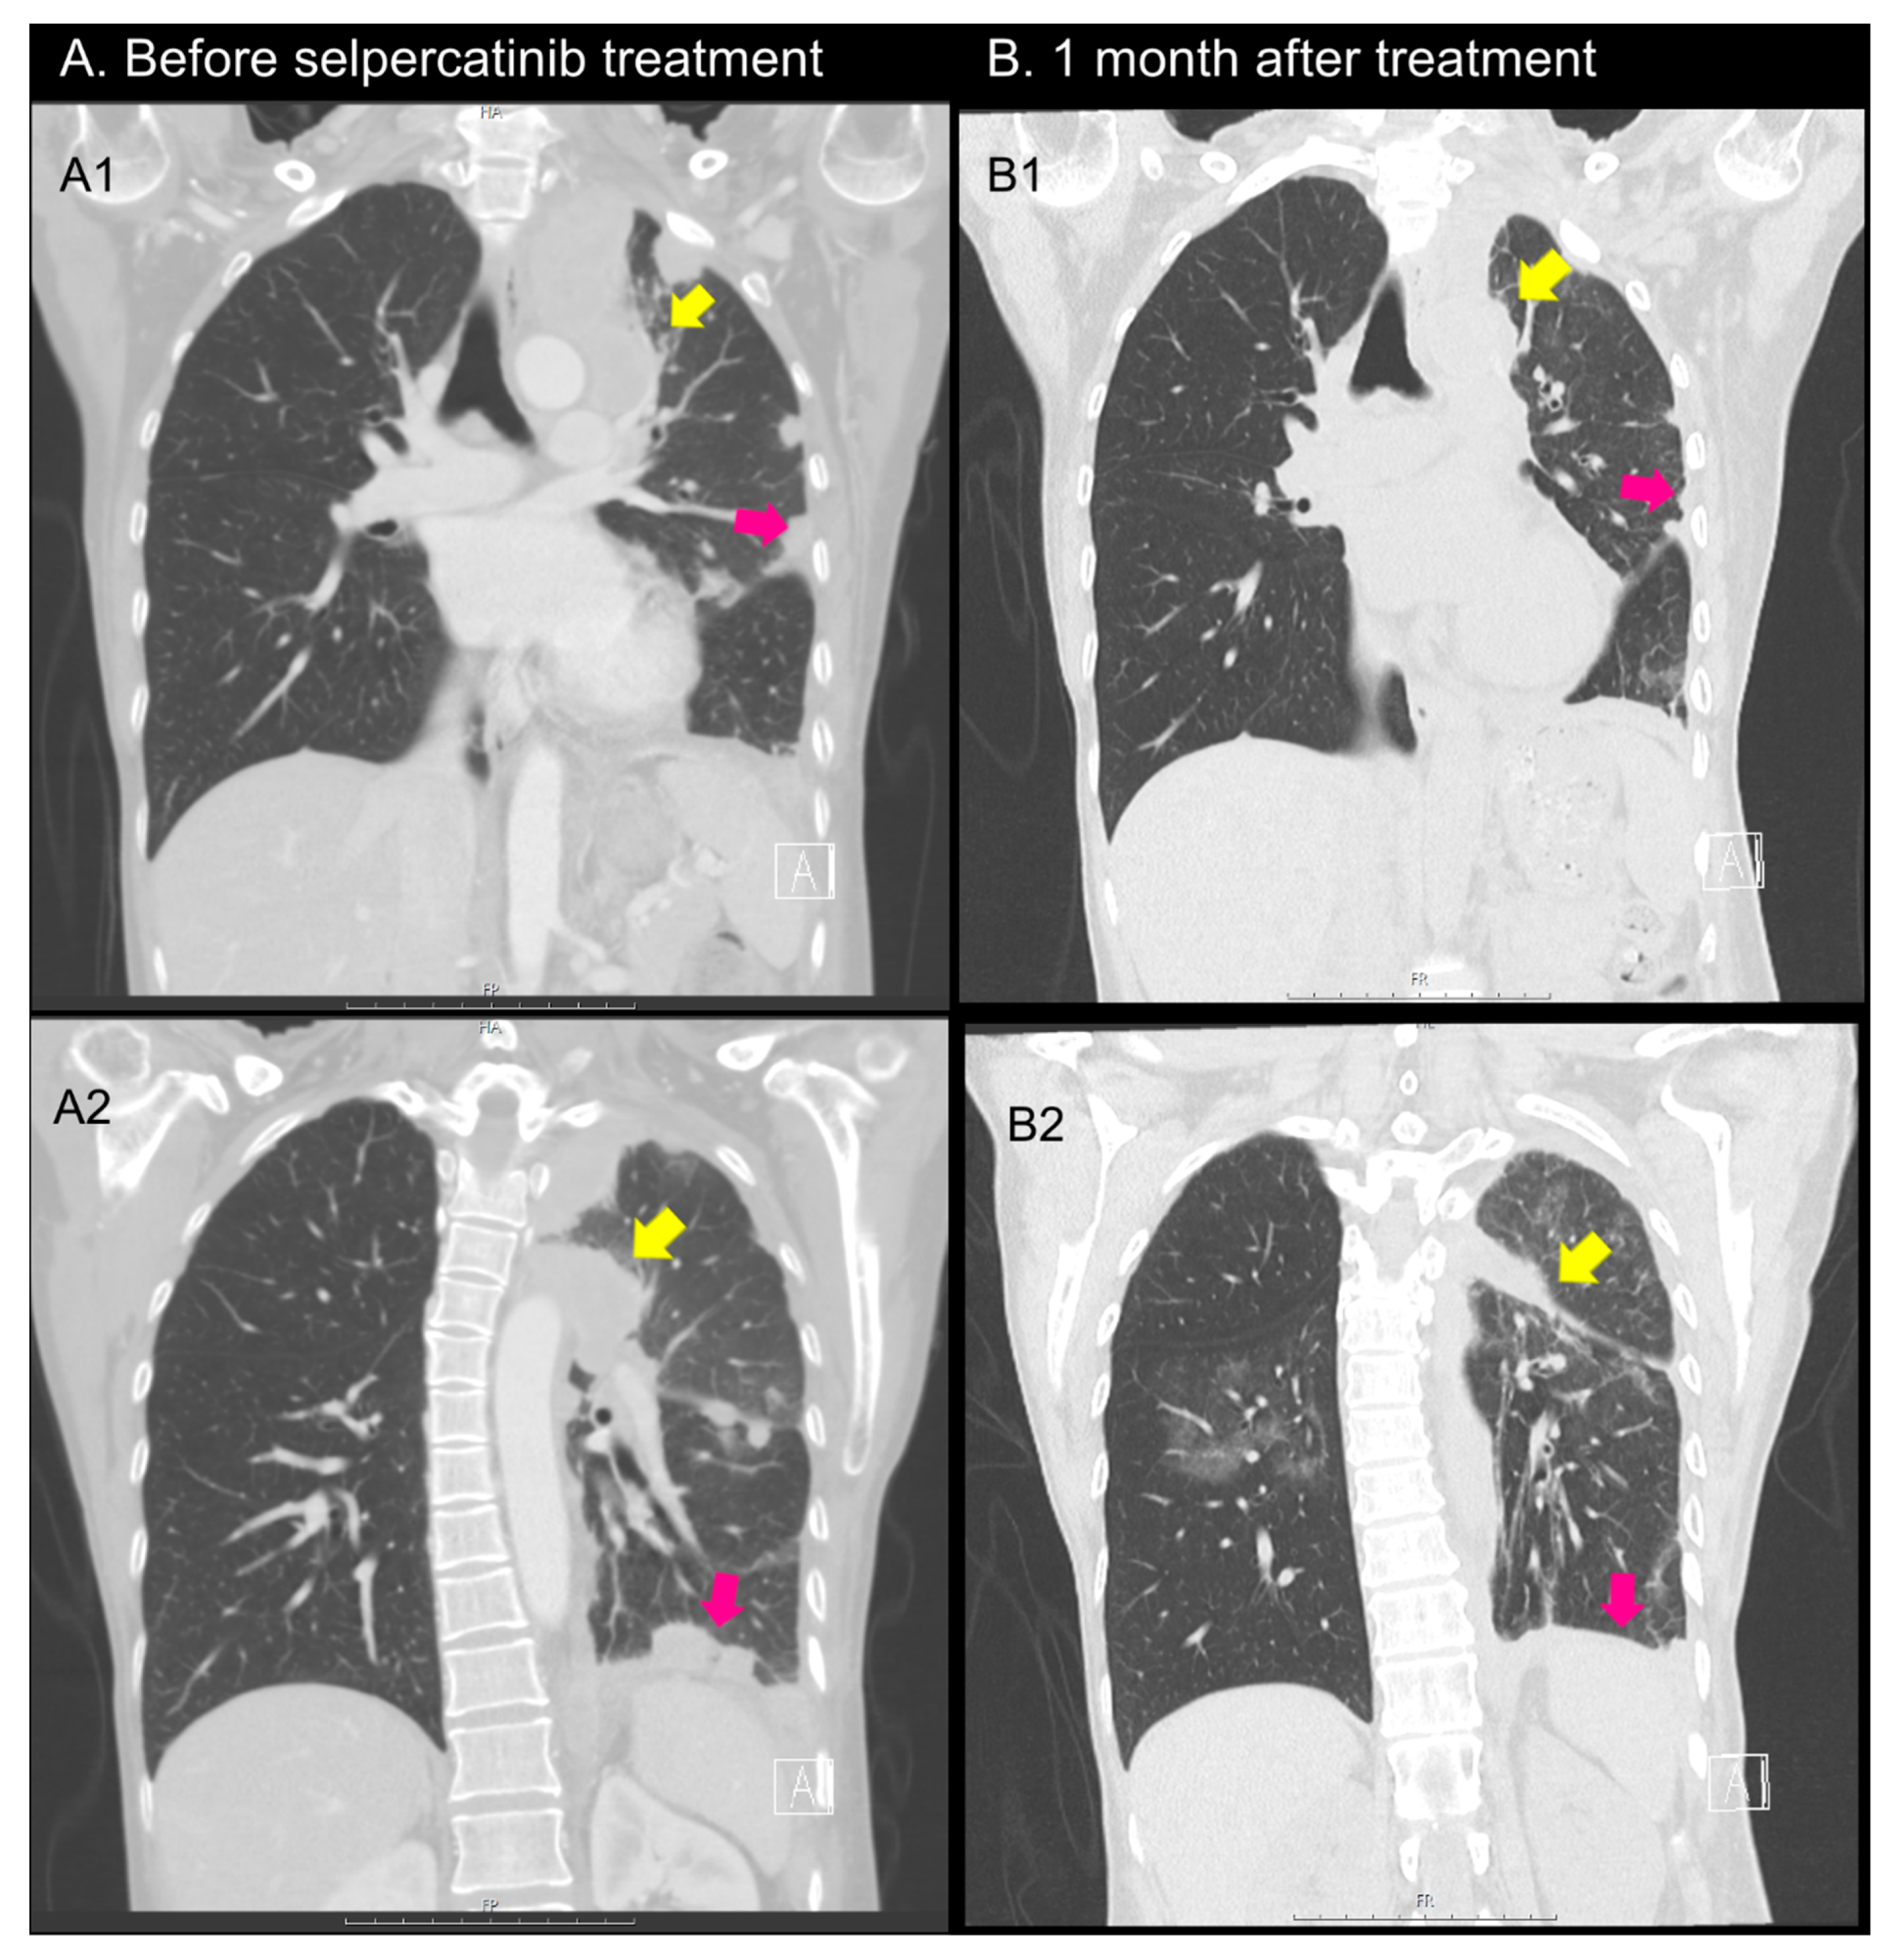

2.1. Case 1

2.2. Case 2

2.3. Case 3

2.4. Case 4